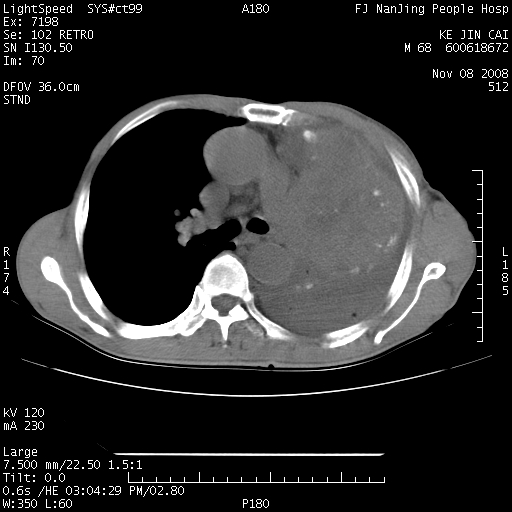

是个很有看头的病例,咋人气那么不旺?没多少人兴趣呢?这个病例几大怪:1   恶性肿瘤侵犯心肌左房怪,心肌一般不会被恶性肿瘤侵犯吧?2   左下肺均匀实变怪,内无含气,有别一般不张实变,含气肺泡完全为液体取代,而非一般不张实变的肺萎陷,冷不丁还以为是肿大的脾脏3   肿瘤本身怪,像tb肺不张4   这么有看头的病例没人气怪。呵呵。

左肺恶性肿瘤侵犯肺动脉,左心房内瘤栓,胸膜转移。

左肺恶性肿瘤侵犯肺动脉,左心房内瘤栓,胸膜转移,少见,学习了。